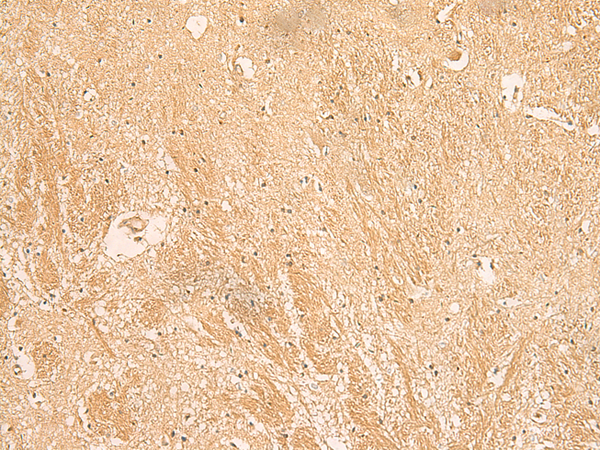

The image is immunohistochemistry of paraffin-embedded Human brain tissue using 47339(MPZL1 Antibody) at dilution 1/30.(Original magnification: 200)